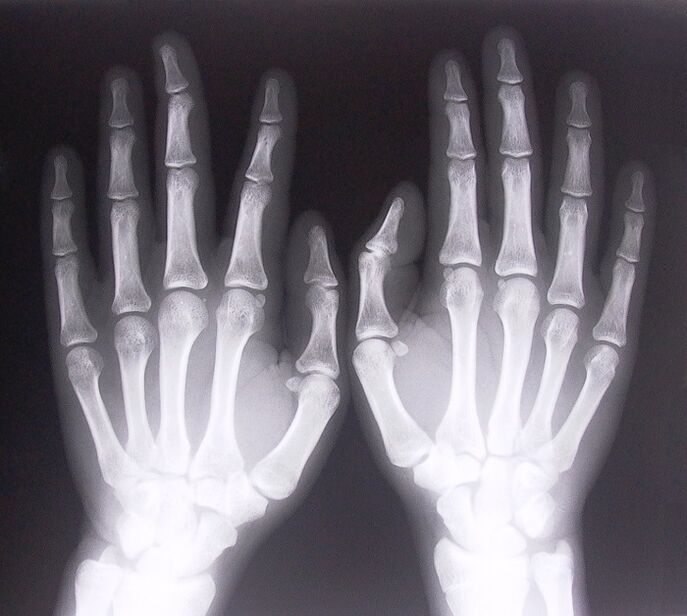

- स्टेनोज़िंग लिगामेंटाइटिस. बीमारी के कारण की पहचान करने के लिए एक्स-रे कराना जरूरी है। लक्षण विशिष्ट हैं: हाथ का दर्दनाक हिलना, भींची हुई हथेली का घूमना। इसके अलावा, एक्सटेंशन के दौरान, क्लिक आमतौर पर सुनाई देते हैं।

- एक्स-रे लें.